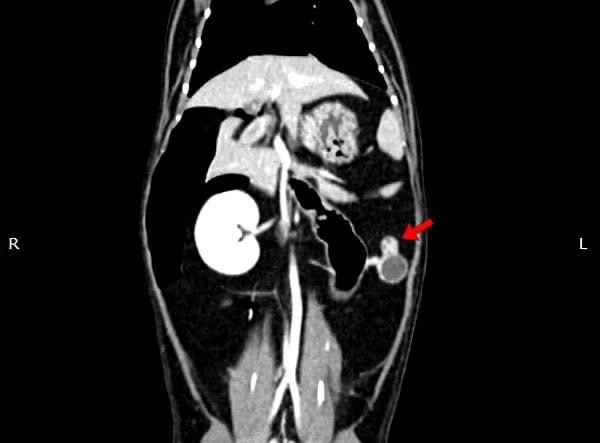

貓咪 卵巢殘留

在他院絕育後仍有發情現象,轉院至築心,經由電腦斷層掃描確認後手術。